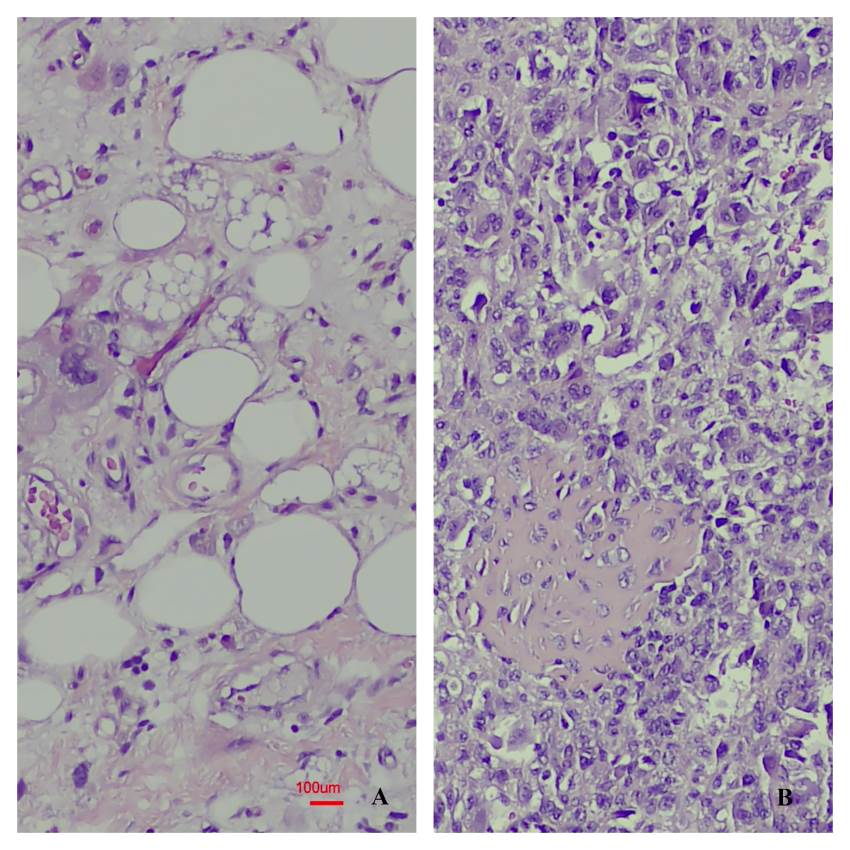

Results: During the specified period, a total of 20 patients were identified, most of whom were male. The kidney was the most frequently affected site. Malignant tumours were diagnosed in 11 patients, and benign tumours in 9. Leiomyosarcoma was the most common malignant tumour, while angiomyolipoma was the most frequently observed benign tumour. Other malignant tumours included rhabdomyosarcoma, liposarcoma, undifferentiated pleomorphic sarcoma, paraganglioma, malignant solitary fibrous tumour, and diffuse large B-cell lymphoma. Benign tumours included angioleiomyoma, schwannoma, renomedullary interstitial cell tumour, leiomyoma, and angiofibroma. Surgical procedures varied depending on tumour type and included excisional biopsy, partial resection, and radical resection. During the follow-up period (ranging from 1 to 38 months), survival was achieved in all patients with benign tumours, whereas three patients with malignant tumours died.